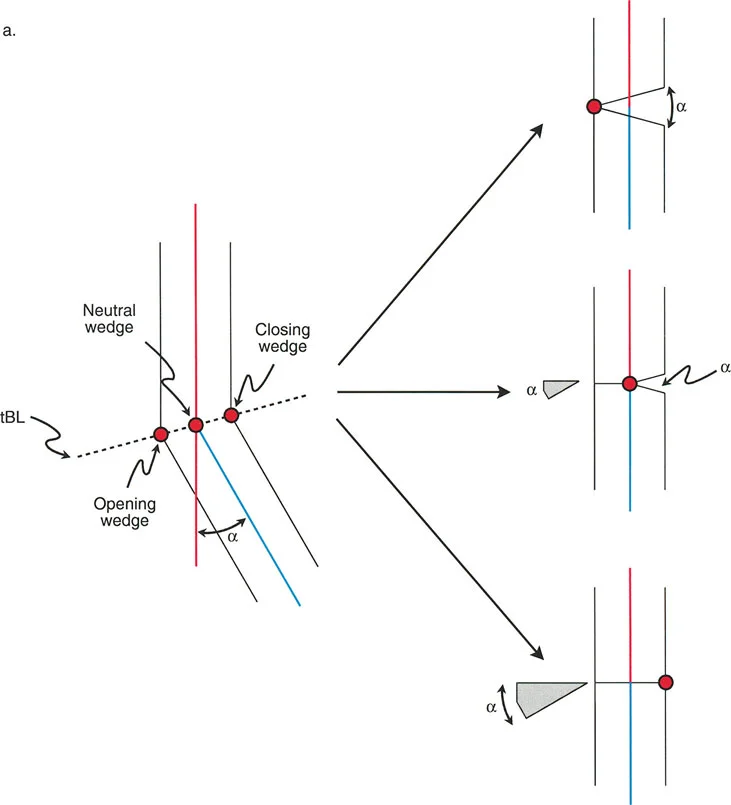

لا يقتصر فهم تفاوت طول الأطراف على مجرد قياسات بسيطة؛ بل يتطلب فهمًا عميقًا ثلاثي الأبعاد لميكانيكا الأطراف السفلية الحيوية، ومبادئ بالي لتصحيح التشوهات – بما في ذلك انحراف المحور الميكانيكي (MAD) ومركز دوران الزاوية (CORA) – واتخاذ قرارات دقيقة ومناسبة لكل مريض بشأن أساليب التصحيح التدريجي مقابل التصحيح الحاد.